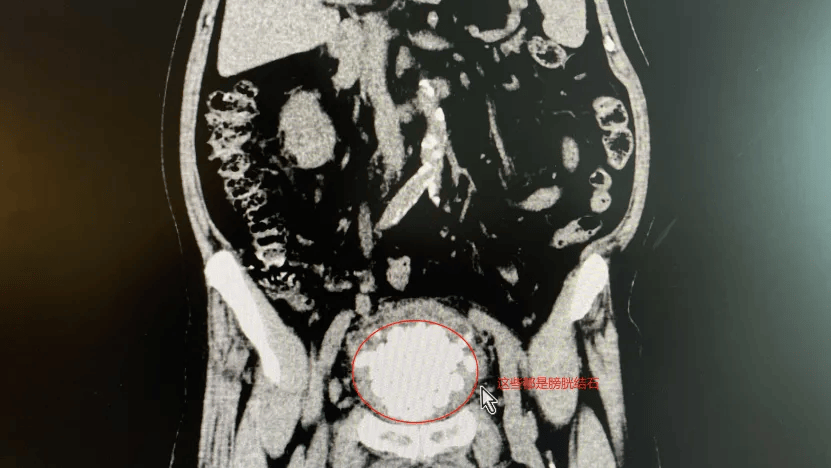

"掏到手酸"!广东祈福医院为87岁老人膀胱取出近300颗结石

图片尺寸831x468